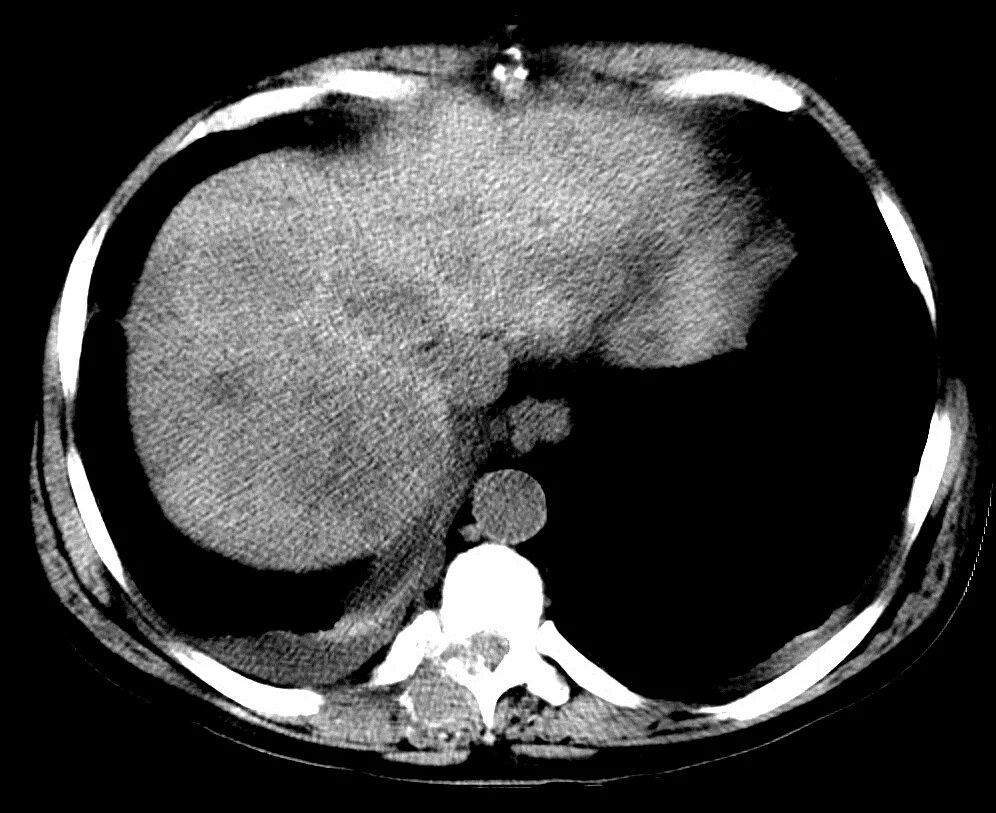

Цирроз печени кт